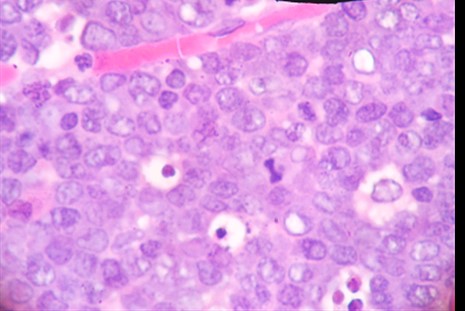

Al examen microscópico se observó: una neoplasia maligna de células redondas, con patrón de cielo estrellado, difuso, células medianas, dispuestas de manera monomorfa con alto índice mitótico, de apéndice cecal. (Figura 2 y Figura 3). Los estudios de inmunohistoquímica demuestran: ACL, CD20 positivos (Figura 4); CD3, BCL2 negativos. Ki 67 positivo en 95% (Figura 5). Otras tinciones para Pankeratina y EBV fueron negativas, diagnosticándose un linfoma Burkitt.

Figura 3 Vista HE 40x de cuerpo de mitosis y cuerpos apoptóticos celular monomorfas homogéneas y núcleos con cromatina grumosa

El diagnóstico radiológico es muy difícil, un diagnóstico probable de neoplasia del apéndice puede sospecharse cuando en la tomografía se nota un incremento del tamaño del apéndice > 3 cm3,6 y la especificidad aumenta cuando se evidencia linfoadenopatia, pero estos hallazgos también son inespecíficos. En el análisis anatomopatológico el estudio macroscópico llama la atención el engrosamiento irregular de la pared apendicular o el efecto de masa. A la microscopía se observa una neoplasia de patrón difuso en cielo estrellado debido al alto índice mitótico y apoptóticos de las células medianas y monomorfas que se disponen de manera homogénea, núcleos con cromatina grumosa, con dos o tres nucléolos (Figura 2 y Figura 3) el cual es confirmado por el estudio de inmunohistoquímica que confirman la positividad para CD20, CD10 (Figura 4), y negatividad de CD3, BCL2, índice proliferativo alto mayor de 95% (Figura 5), alteración citogenética de c-Myc10.